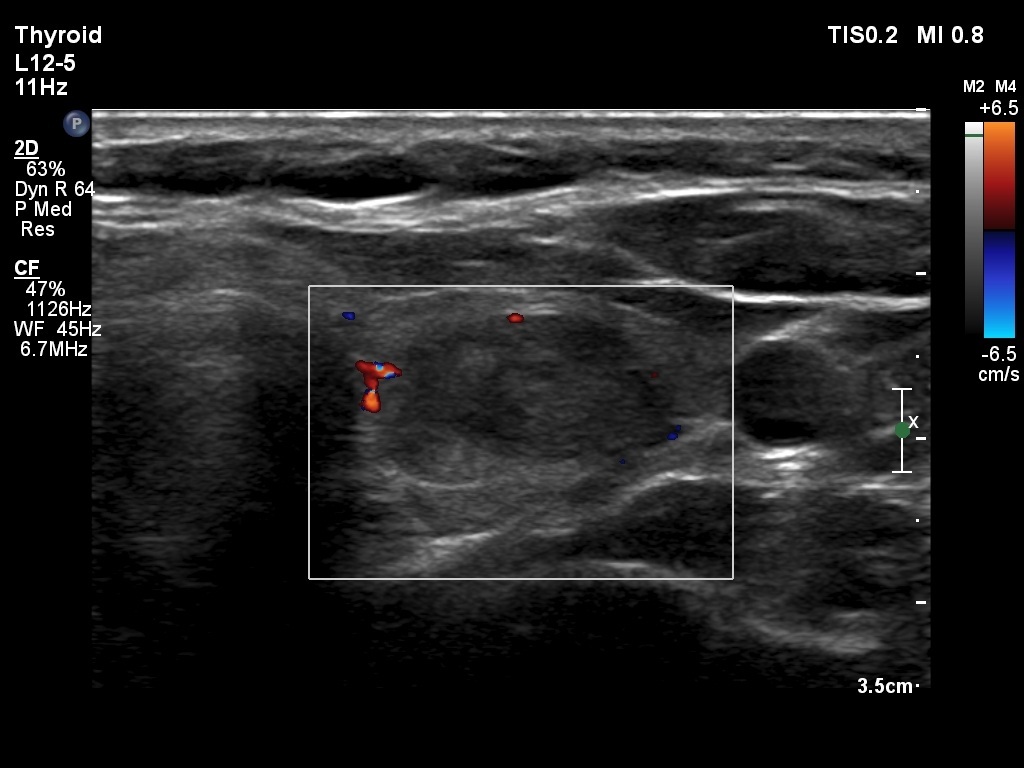

First examination (1st and 2nd rows of images)

Ultrasonography. The thyroid was echonormal. There was a moderately hypoechogenic, inhomogeneous nodule in the part of the left lobe. The nodule presented a type 3 vascular pattern.